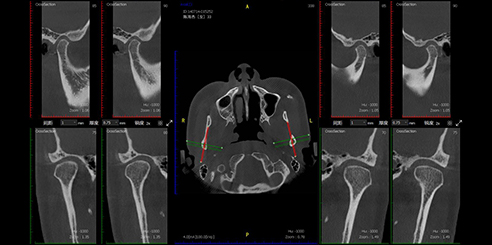

Next, Nerve Detection with Dental CBCT (AI+Nerve)

The system automatically identifies and labels the neural tube within the CT image.

This function simplifies diagnosis and supports more precise surgical planning.

T-MAR Metal Artifact Reduction in LargeV Dental CBCT

With the new T-MAR module, the system automatically removes metal artifacts and corrects image distortions intelligently.

Hence, the final images remain clear, accurate, and clinically reliable.